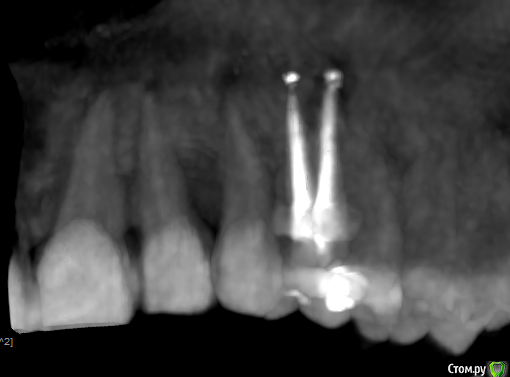

Прикрепляю скриншоты КТ. Подскажите, пожалуйста, что это может быть под красной стрелкой на снимках 2 и 3?

Рентген - это дополнительный метод исследования и диагностики. Поэтому только на основании снимка и субъективных ощущений пациента невозможно поставить диагноз и дать полный правильный ответ. Мне было бы важно также посмотреть состояние соседних зубов, особенно зуба 1.5 (перкуссия, подвижность, состояние тканей пародонта, витальность, патологическая стираемость, температурные пробы...). Делать упор только на леченный 1.4 зуб неправильно. Хотя допускаю, что и он может быть причиной всех болезненных ощущений (например трещина в корне, вывод материала, перфорация боковой стенки, близость гайморовой пазухи, лор статус, неврологический статус.... Да чего только не может быть).

КТ также необходимо внимательно рассматривать полностью, а не отдельные "срезы".

Иногда причиной болей может быть локальный пародонтит. Например между зубами 1.4 и 1.5 (как Вы и писали в начале топика). Снимаем воспаление, и вся симптоматика уходит (было не один раз такое в моей практике). Поэтому при подобных жалобах также провожу локальное исследование тканей пародонта, в том числе пародонтальных карманов и межзубных промежутков наиболее вероятных "зачинщиков" боли.